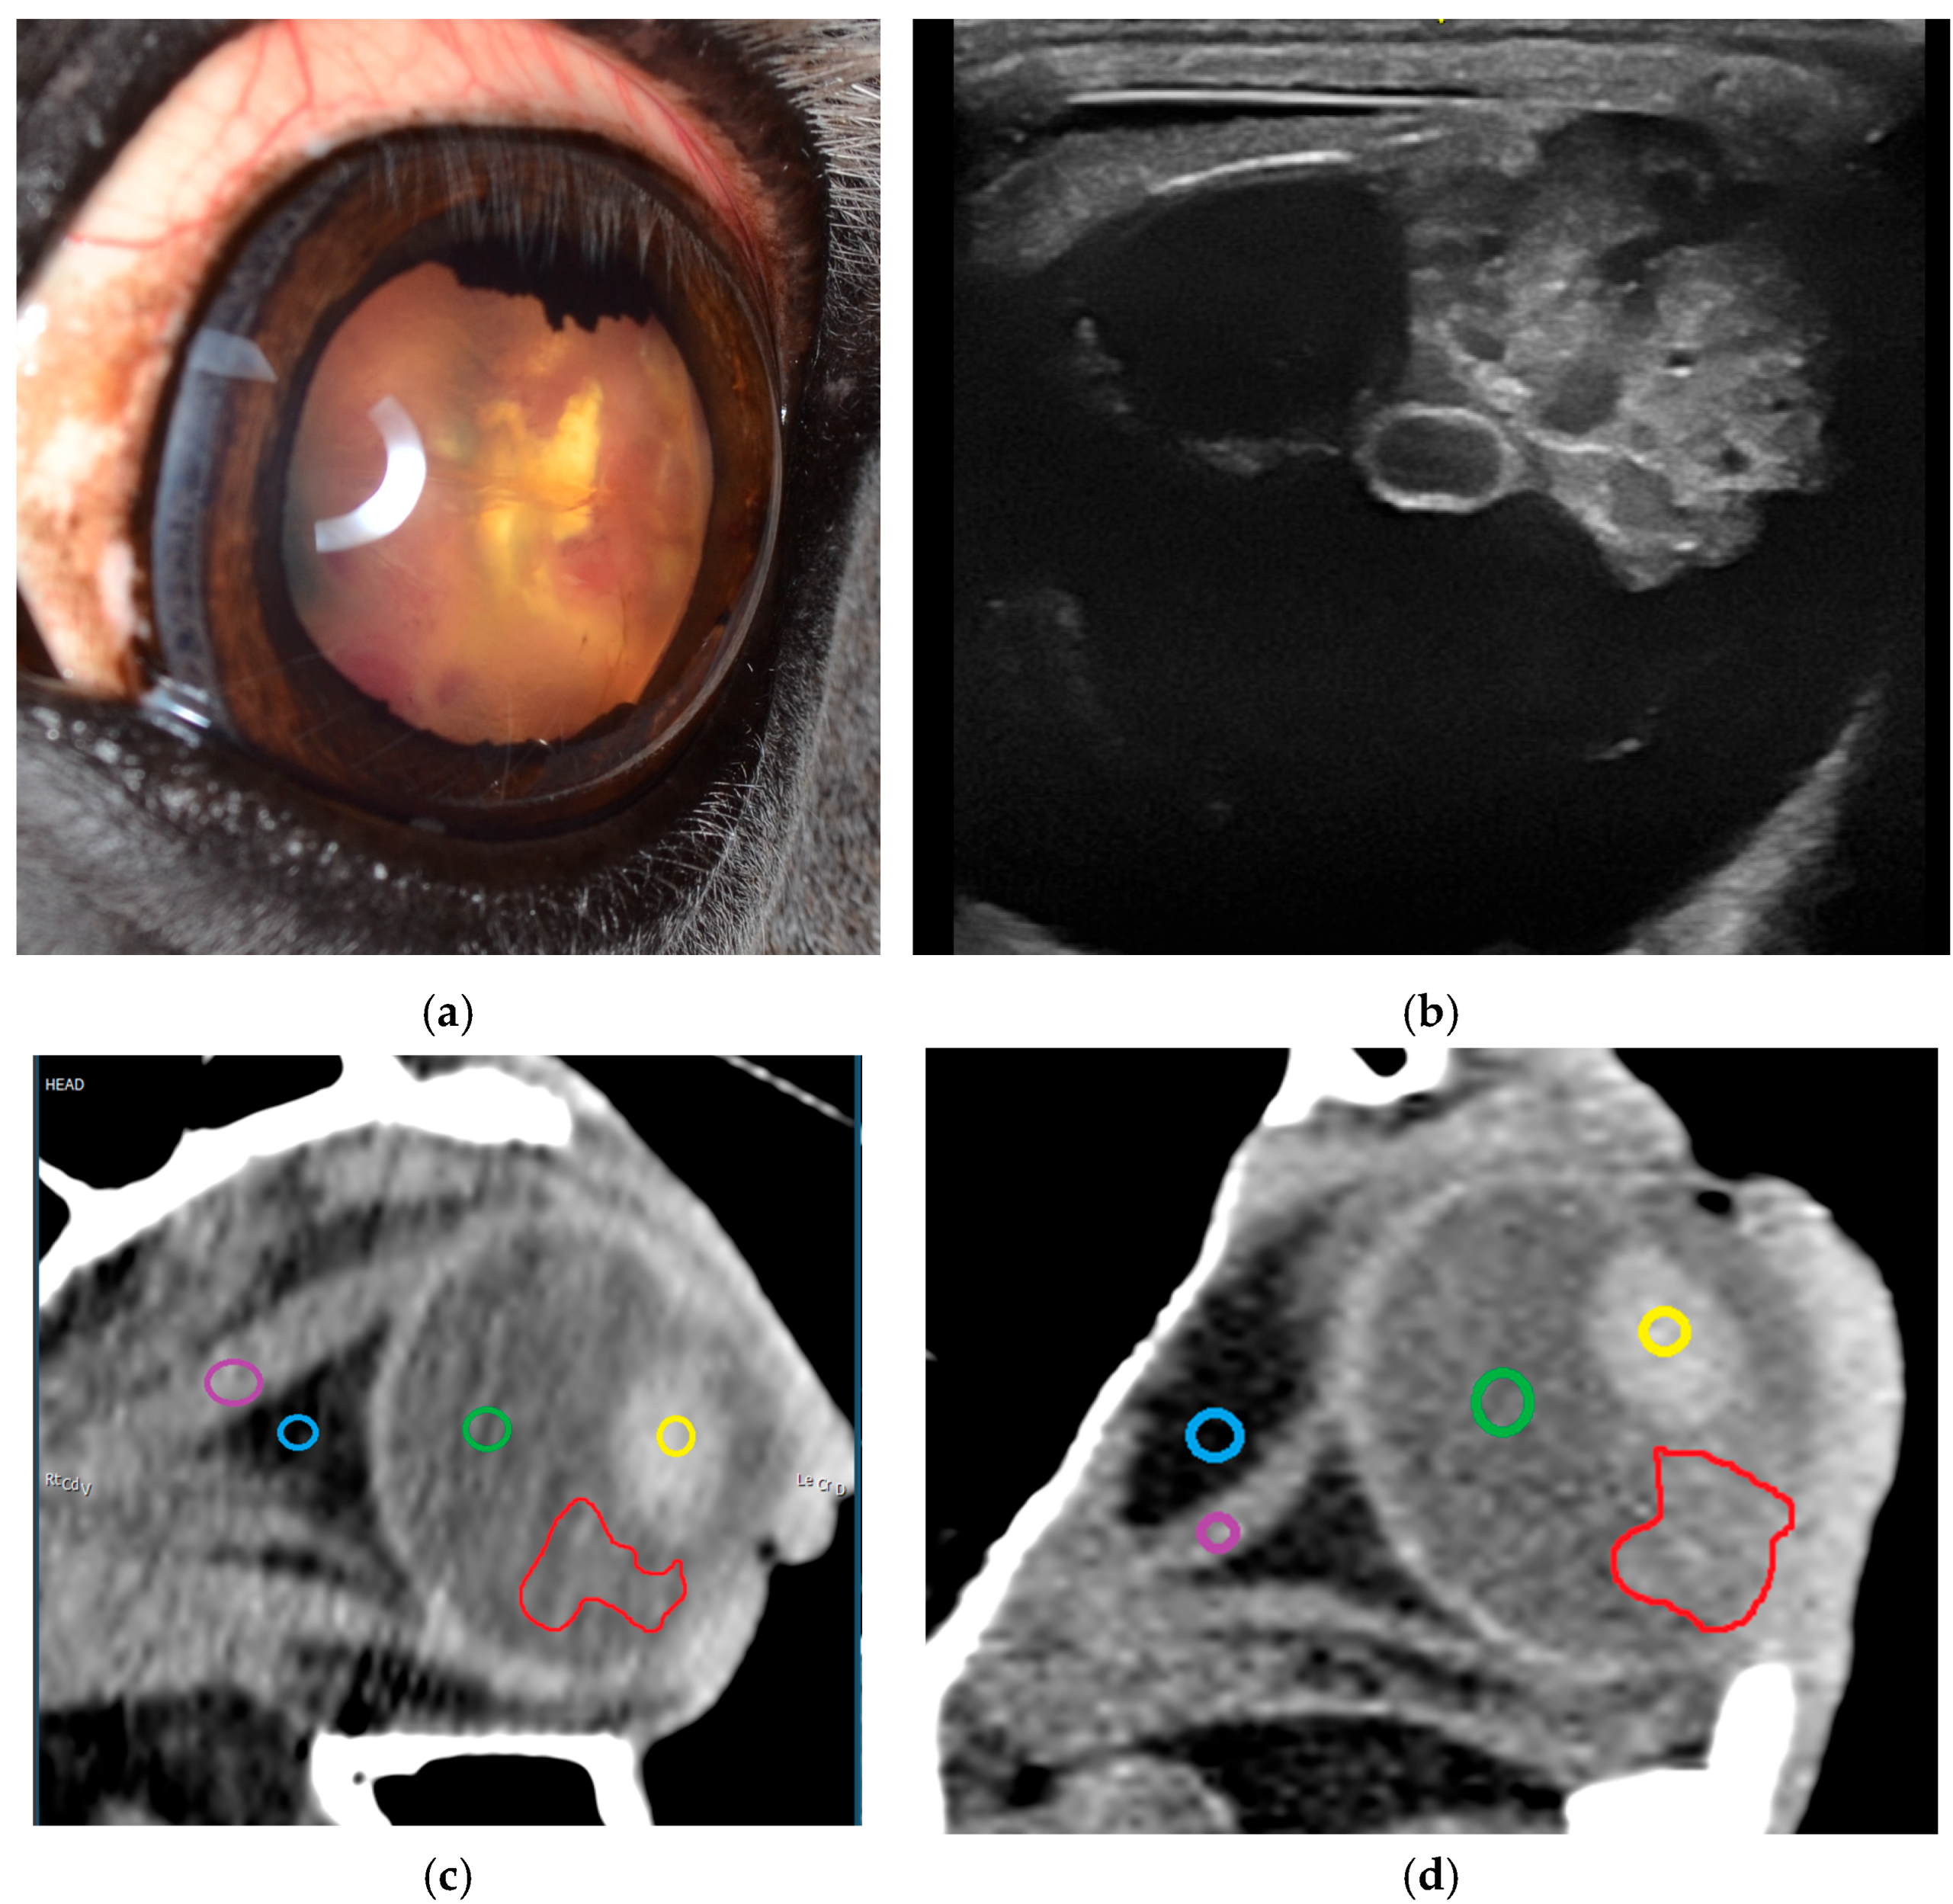

3.2.1. Ultrasonography

3.2.2. Sectional Imaging